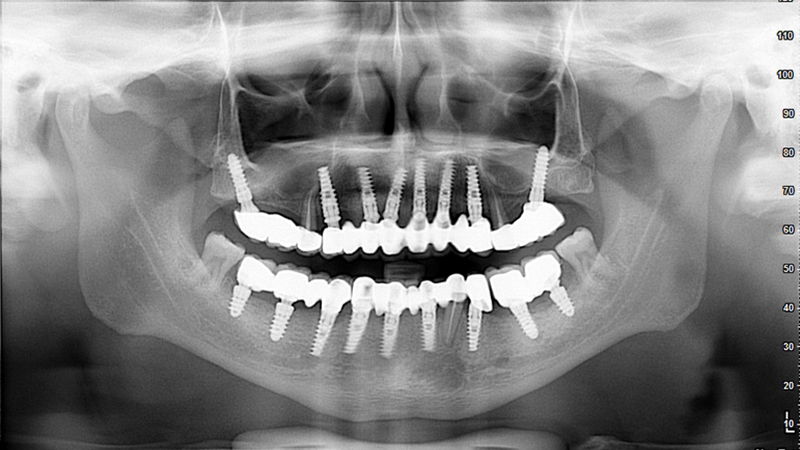

FULL MOUTH REHABILITATION with IMPLANTS

Implant Patients